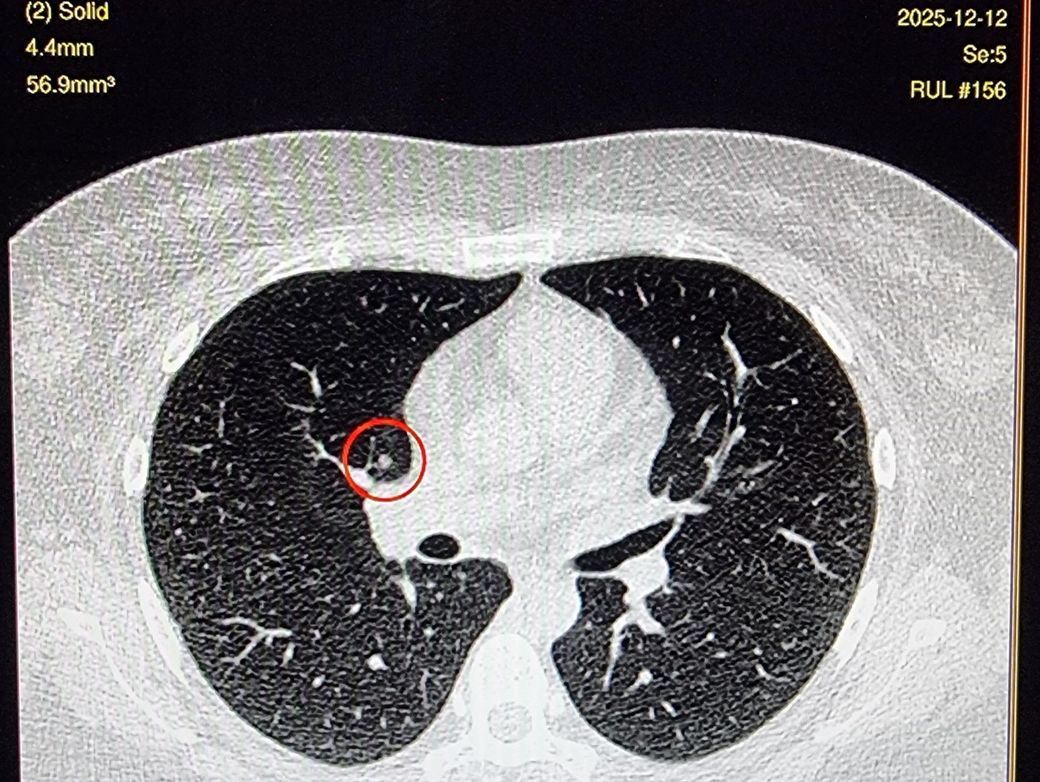

일단은 판독전 간유리라고 들었는데

3thk 적혀있는거 제외하고 1thk입니다

밝고 선명한건 AI가 발견한것으로 두번째 사진이랑 같은거 같습니다.

둘째 영상과 셋째 영상은 둘다 간유리음영으로 보셔도 될 것 같습니다.

따라서 현 영상만으로 보다면 간유리음영이라고 생각을 하셔도 될 것 같으며

일부 고형성 결절 부분을 포함하고 있다는 걱정은 굳이 하지 않으셔도 될 것 같습니다.